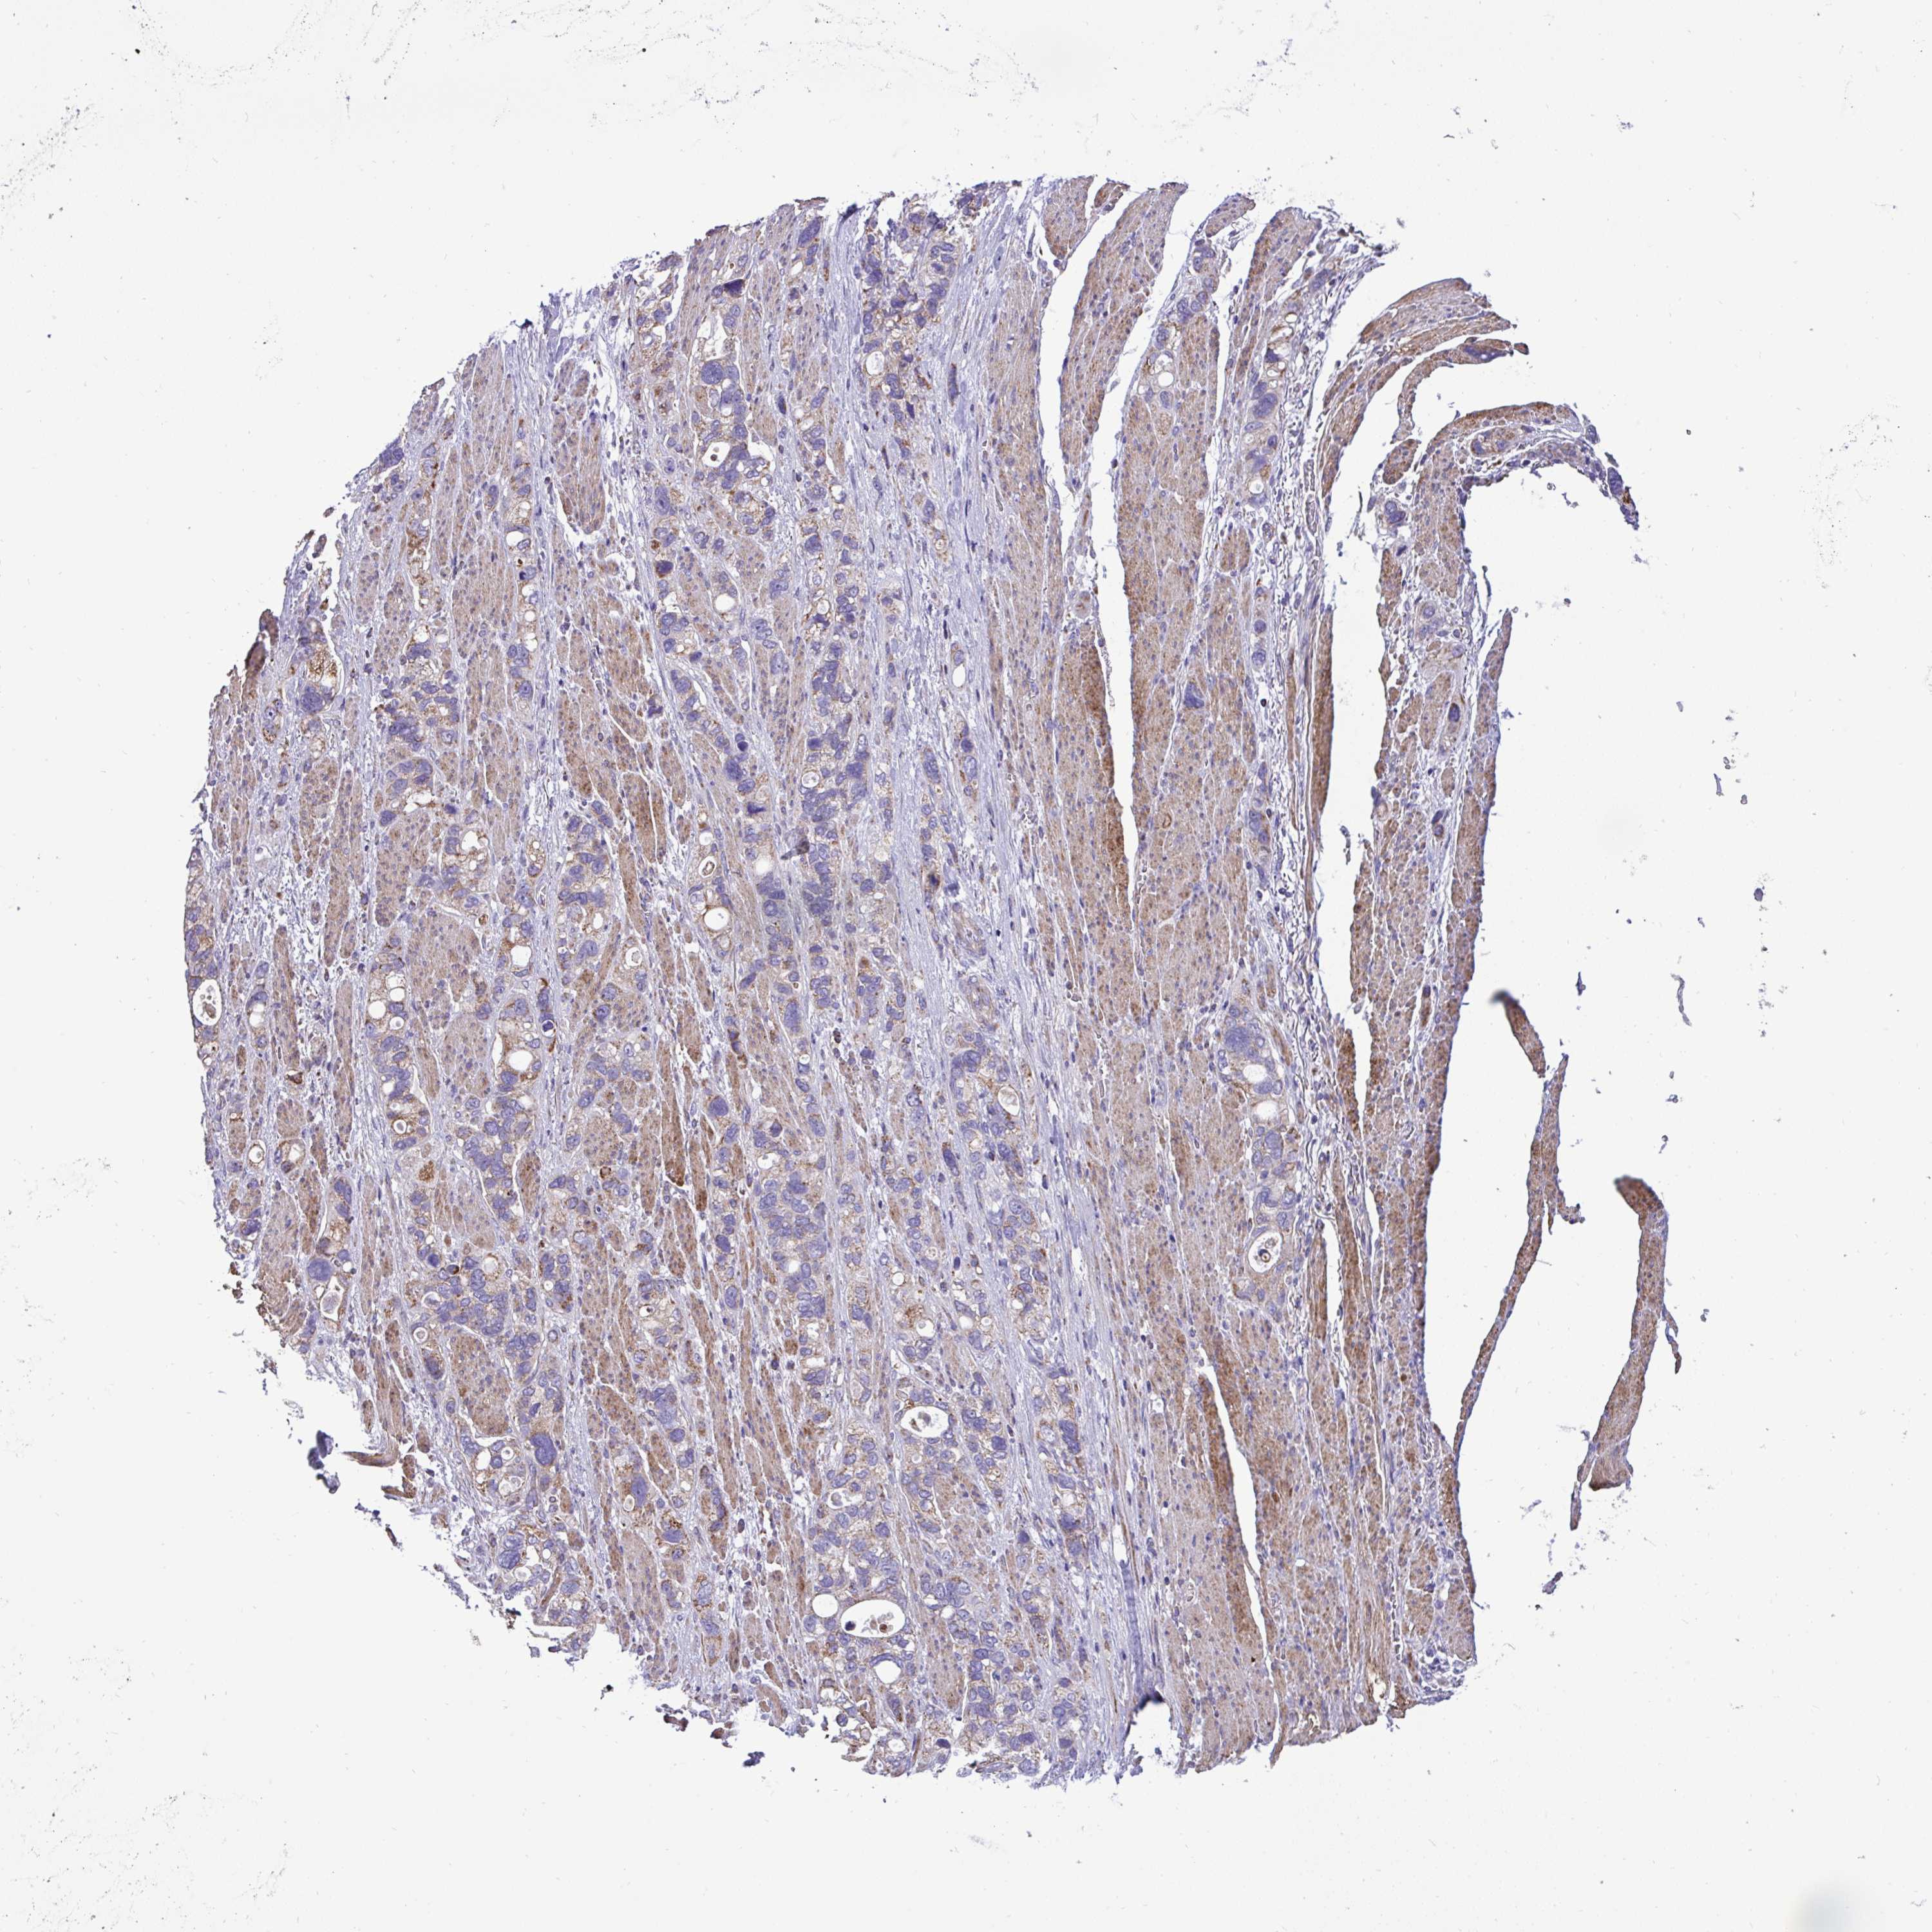

STOMACH CANCER - Protein expressioni

A mouse-over function shows sample information and annotation data. Click on an image to view it in a full screen mode. Samples can be filtered based on level of antibody staining by selecting one or several of the following categories: high, medium, low and not detected. The assay and annotation is described here.

Note that samples used for immunohistochemistry by the Human Protein Atlas do not correspond to samples in the TCGA dataset.

Antibody stainingi

Antibody staining in the annotated cell types in the current human tissue is reported as not detected, low, medium, or high, based on conventional immunohistochemistry profiling in selected tissues. This score is based on the combination of the staining intensity and fraction of stained cells.

Each image is clickable and will lead to virtual microscopy that enables deeper exploration of all samples and also displays staining intensity scores, fraction scores and subcellular localization as well as patient and tissue information for each sample.

Antibody HPA057267

Antibody HPA058086

Staining

High

Medium

Low

Not detected

Intensity

Strong

Moderate

Weak

Negative

Quantity

>75%

75%-25%

<25%

None

Location

Nuclear

Cytoplasmic/membranous

Cytoplasmic/membranous,nuclear

Adenocarcinoma, NOS